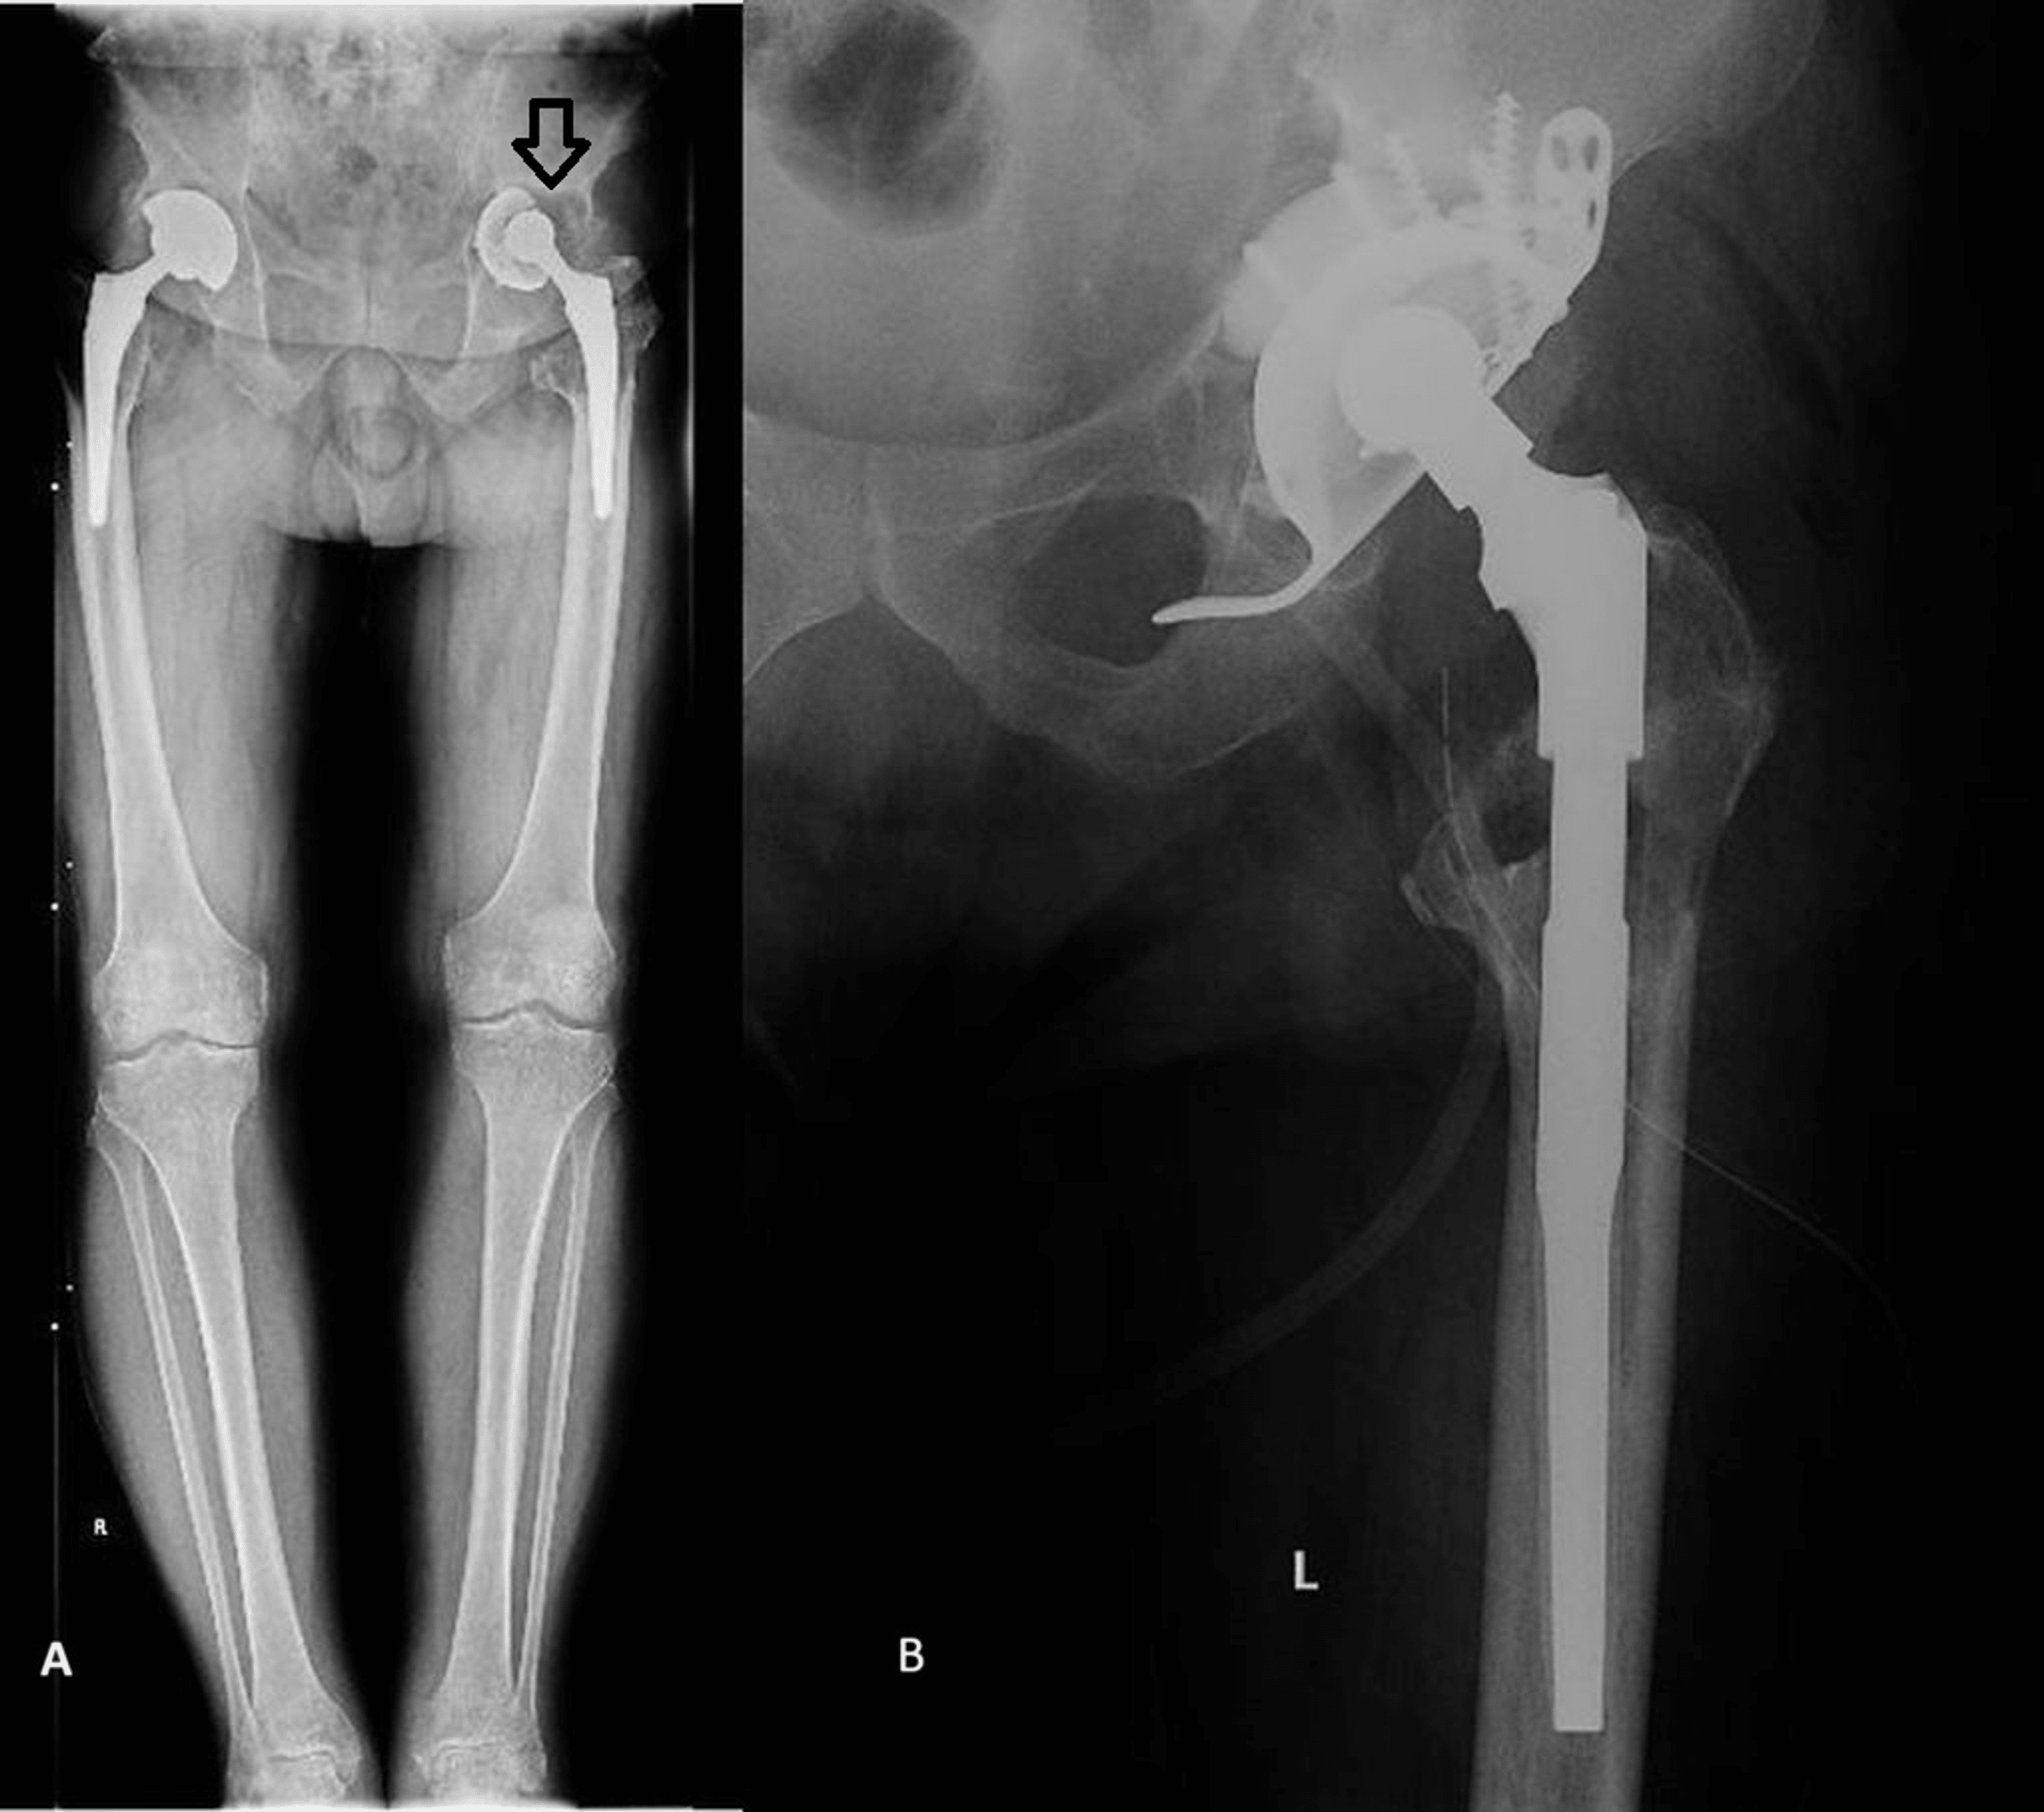

Hip revision in the foregoing patient at 6 months postoperatively. A... Download Scientific How Dangerous Is Hip Revision Surgery While revision hip replacement can improve your quality of life, it is not without risks. How common is hip revision surgery?. Damage to bone and soft tissue around the hip may make it difficult for the doctor to use standard primary hip implants for revision hip replacement. In the united states, there are approximately 18 revision hip replacements performed for. How Dangerous Is Hip Revision Surgery.